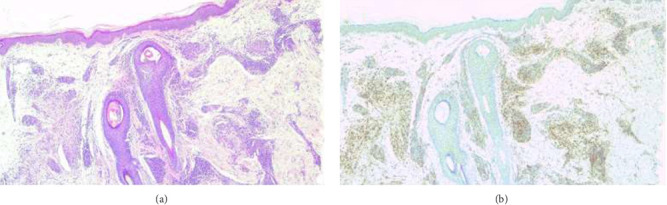

Granuloma annulare (GA) is an inflammatory and granulomatous dermatosis characterized by annular erythematous papules/plaques frequently localized in acral regions. Proinflammatory cytokines such as tumor necrosis factor-alpha (TNF-α) and interferon-gamma (IFN-γ), which are released by T helper 1 (Th1) lymphocytes inducing macrophages, are thought to play a role in its pathogenesis. Lichen planus (LP) is an inflammatory dermatosis characterized by pruritic scaly purple papules, often on the wrists and ankles, and can also affect mucosa, hair, and nails. T-cell-mediated proinflammatory cytokines such as IFN-γ and TNF-α, which are released by macrophages upon Th1 stimulation, have been implicated in the pathogenesis of LP, as in GA. A new treatment option is needed in the treatment of these diseases due to suboptimal results and adverse side-effect profiles with conventional treatments. Apremilast is a phosphodiesterase-4 (PDE4) inhibitor and inhibits the production of various inflammatory mediators such as IFN-γ, TNF-α, IL-2, IL-5, IL-8, IL-12, and leukotriene B4. This molecule has three Food and Drug Administration (FDA) approved indications: moderate to severe plaque psoriasis, psoriatic arthritis, and oral ulcers associated with Behcet's disease. Apremilast exhibits a favorable side-effect profile compared to conventional treatments and is a good treatment option with its ability to reduce cytokines implicated in the pathogenesis of GA and LP. Here, we report the case of a 55-year-old woman in whom apremilast treatment led to an almost complete resolution of her GA and LP.